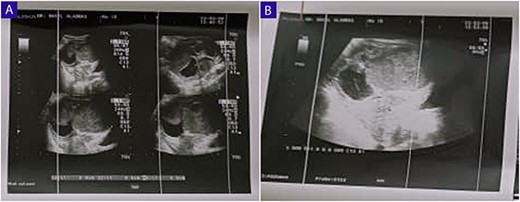

A 25-year-old woman, nulliparous, presented to our gynecology clinic with complaints of intermittent low-grade fever with lower abdominal pain, most severe in the left iliac fossa, and distension over the last 2 months. These symptoms were not associated with any gastrointestinal or urinary complaints. The patient had a history of a left ovarian cyst and underwent a laparoscopy 4 months ago, initially relieving her symptoms. However, after 2 months, the symptoms recurred, accompanied by a high fever with a high C-reactive protein (CRP) level. Due to the inflammatory symptoms and the ultrasound findings, the condition was diagnosed as an ovarian abscess, and a course of antibiotics was administered. However, the patient did not show improvement, and a persistent low-grade fever accompanied by consistently elevated CRP levels continues to be observed. Her menstrual history was normal with regular periods. There was no family history of breast, ovarian, or endometrial cancer. On physical examination, the abdomen was tender, and a palpable mass was felt in the left iliac fossa region. Pelvic examination revealed a normal-sized non-pregnant firm uterus and fullness in the cul-de-sac and left adnexa. Subsequent investigations showed hemoglobin (Hb) of 10.9 g/dl, total leucocytes count of 15.7 x 10 g/l, erythrocyte sedimentation rate of 56 mm/h, CRP level of 24.6 mg/l (normal range 0–6 mg/l), and CA-125 (cancer antigen 125) of 12.5 U/ml (normal range 0–20.1 U/ml). Ultrasound of the abdomen and transvaginal ultrasound were performed revealing a 9 cm x 6 cm thick-walled cystic mass in the left pelvic region. The mass exhibits irregular borders, a heterogeneous echotexture, and is multilocular with numerous septations (Fig. 1). The right ovary was not visualized separately. The patient underwent a unilateral salpingo-oophorectomy, and intraoperative findings confirmed a large cystic mass with a nodular appearance arising from the left ovary (Fig. 2) (Video 1). The right ovary appeared grossly normal and was preserved to maintain hormonal function. On gross examination, the surgically excised specimen consisted of a cystic mass measuring 9 cm x 7 cm x 5 cm, exhibiting nodules. Upon sectioning, the mass had a thick outer wall and was multilocular with variably sized septa, containing thick gelatinous mucoid material characteristic of a mucinous tumor. No solid areas or papillary structures were noted. Surprisingly, the adjacent tissue displayed yellowish nodules and areas of firm induration (Fig. 3). Microscopic examination of the mass revealed cystic glands lined by a single layer of non-ciliated columnar epithelium with abundant intracellular mucin. No cytologic atypia or mitotic figures. Papillary components and stromal invasion were not identified. Subepithelial-marked foamy macrophages, fibrosis, and chronic inflammatory infiltrates were observed (Fig. 4). Based on histopathological features, a diagnosis of mucinous cystadenoma with xanthogranulomatous oophoritis was made. Postoperatively, the patient’s recovery was uneventful, and follow-up assessments at 6 months revealed no evidence of recurrence.

(A and B) Ultrasound of the abdomen and TVUS reveals a 9 cm x 6 cm thick-walled cystic mass in the left pelvic region; the mass exhibits irregular borders, a heterogeneous echotexture, and is multilocular with numerous septations.